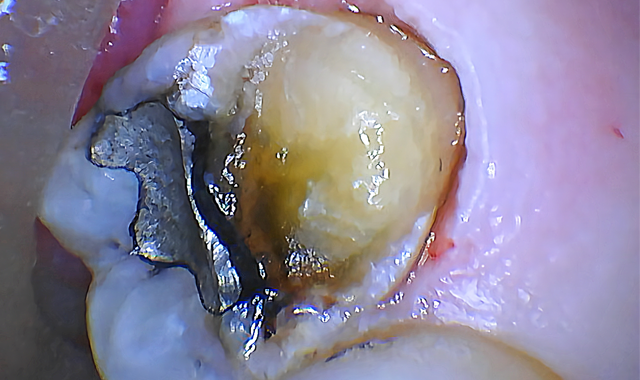

Fig. 3

Using the 1 mm spot size with cutting speed between 30-50 percent and 20 percent mist, the gingival tissue was ablated until the planned restorative margin could be seen (Fig. 3).

I then proceeded to remove bone using the 0.75 mm spot size with 80 percent cutting speed and 50 percent mist.

The laser was aimed down the long axis of the tooth to remove bone between the tooth and soft tissue.

The bone was ablated until the osseous crest was 2 mm apical to restorative margins (Fig. 4). Both steps were completed with virtually no bleeding.